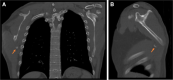

Inferior scapula avulsion fractures are rare injuries, with few cases reported and only a small number managed operatively discussed in the literature. We report the case of a man in his 40s who fell from a height and presented with right-sided scapular winging and point tenderness at the inferior pole of his right scapula with no neurological deficit. Radiographs and CT diagnosed avulsion fracture of the inferior scapula. The patient underwent surgical fixation and, following a course of physiotherapy, successfully recovered with no residual winging and full range of movement.